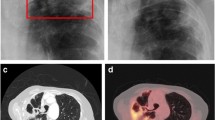

Several studies have documented the CT imaging findings of children with IPA (Table 1) [3, 9, 10, 23,24,25], predominantly in children with malignancy or undergoing HSCT. Most studies included a small number of patients, with one exception which described the CT and or plain radiograph findings in 110 children with IPA [3]. Similar to adults, nodular opacities are most frequently described (59–100%), followed by wedge shaped/segmental or lobar consolidation (21–63%). Cavitation (0–43%) and the air crescent sign (0–21%) are less frequently seen (Fig. 1). The prevalence of the halo sign is variable ranging from 0 to 100% in individual series.

Imaging findings in invasive pulmonary aspergillosis: A, B—6 month old with acute lymphoblastic leukaemia complicated by Aspergillus fumigatus infection showing A left upper lobe wedge shaped/segmental consolidated and right upper lobe nodule with surrounding ground glass halo and B right upper lobe nodule with central cavitation; C, D—8 year old with acute lymphoblastic leukaemia complicated by disseminated Aspergillus flavus infection showing C left lower lobe nodule at diagnosis with D evolution to air crescent sign on follow up imaging

Cavitation and the air crescent sign appear in later stages of infection in neutropenic adults, occurring concurrently with bone marrow recovery [14, 30]. Similarly, cavitation of lesions during marrow recovery has been documented in children with IPA on plain radiographs [32]. Amongst paediatric CT studies, the analysis by Taccone et al. which reported the highest prevalence of cavitation (43%) included findings on follow up CT studies, noting progression to cavitation in a number of cases 2–3 weeks after treatment, coinciding with neutrophil recovery [10]. In paediatric studies including initial diagnostic CT only, cavitation occurs in less than a quarter of cases and the air crescent sign is infrequent (0–3%) (Table 1). Notably, prevalence of cavitation did not significantly differ between age groups in the largest paediatric series to date [3]. Considering the low prevalence in children and overall low specificity of these signs [14, 15], the utility of the air crescent sign and cavitation as individual findings is limited in children with suspected IPA.